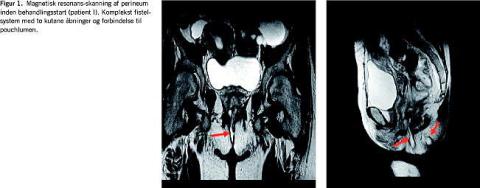

I. En 52-årig kvinde med UC blev kolektomeret i 2002, og i 2005 proktektomeret med anlæggelse af IPAA. Herefter udviklede hun et komplekst pouchvaginalt fistelsystem (seFigur 1 ). Operationspræparatet blev revurderet, og diagnosen UC sikret. Primær behandling med Setonsutur og langvarig ciprofloxacinkur var uden tilfredsstillende effekt, og patienten udviklede samtidigt enteropatisk artropati. IFX-behandlingen påbegyndtes i 2006, hvilket havde en umiddelbar og god effekt på de anogenitale samt specielt på de ekstraintestinale gener, som forsvandt fuldstændigt. Herefter påbegyntes også azathioprinbehandling. Patienten modtager stadig IFX med otte ugers interval. Fistlerne persisterer, men nu uden sekretion eller øvrige gener.